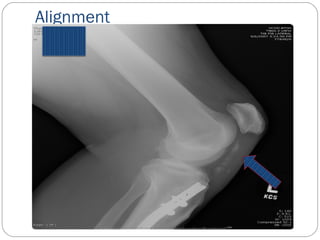

A-B-C-D

A- Alignment- is the bone in good general

Alignment